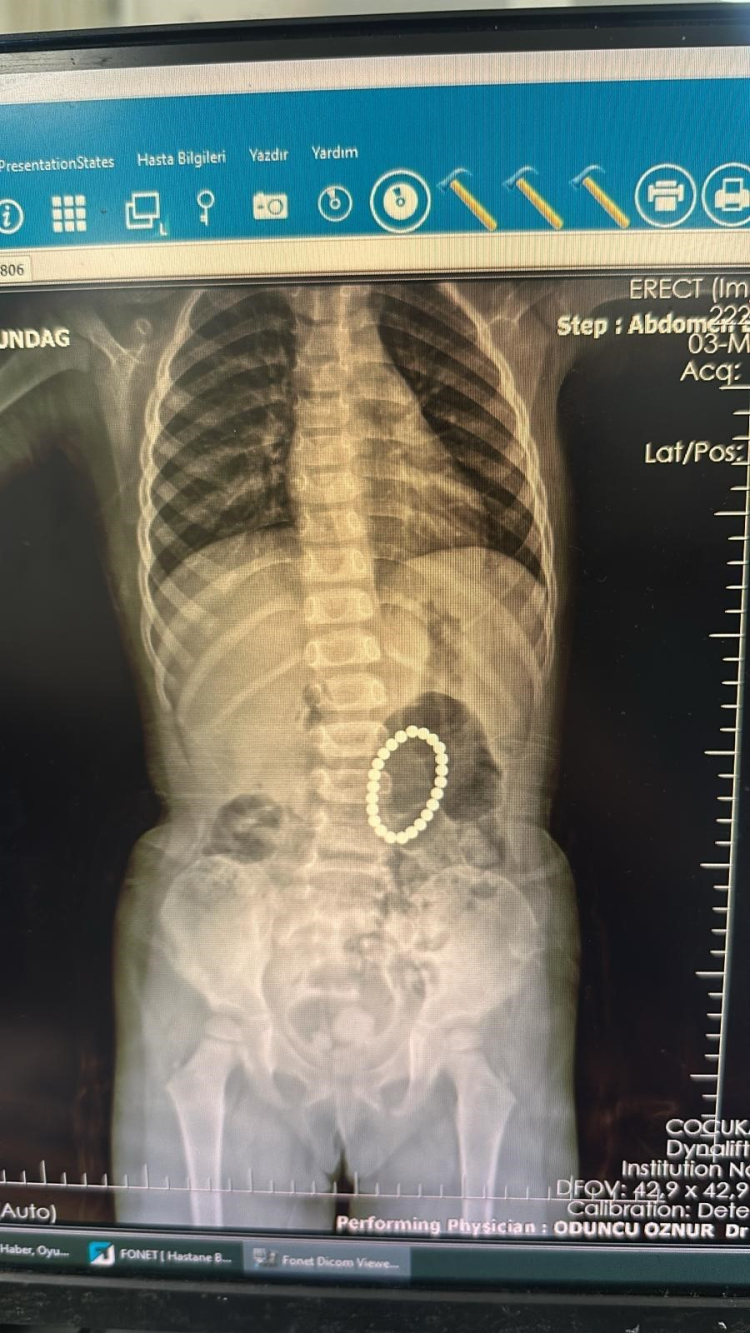

Şırnak'ta yoğun karın ağrısı şikayeti ile önce Cizre Devlet Hastanesine ardından da Şırnak Devlet Hastanesine götürdükleri kızları Rumeysa Altundağ (4), Batman Eğitim ve Araştırma Hastanesine sevk edildi. Batman'a getirilen Rumeysa Altundağ'ı muayene eden Batman Eğitim ve Araştırma Hastanesi Çocuk Cerrahisi Doktor Selim Özkaya daha sonra hastaya endoskopi yaptı. Yapılan endoskopide küçük kızın bağırsaklarında ve midesinde bileklik şeklinde yabancı cisimlerin olduğu belirlendi. Ameliyata alınan Rumeysa Altundağ'ın bağırsakları ve midesinden 24 adet renkli oyuncak mıknatıs çıkartıldı.

İlk defa böyle bir vaka ile denk geldiklerini belirten Doktor Selim Özkaya, yapılan ameliyatın ardından başarılı bir şekilde tamamlandığını söyledi. Mıknatısların bağırsaklarda kısmen delinmelere neden olduğunu belirten Dr. Özkaya, "Hastamız 4 yaşında kız hasta. Yoğun karın ağrısı nedeniyle Şırnak'ta devlet hastanemize başvurmuş, yapılan tetkiklerinde yabancı cisim yuttuğu tespit edilmiş. Bunun üzerine endoskopi yapılmak üzere hastanemize Gastroentoloji bölümüne sevk edildi. Endoskopi sırasında tespit edilen yabancı cisimlerin renkli mıknatıslar olduğu, yarısının da midede gözükmediği görüldü. Hastamız 24 tane renkli küçük mıknatıs yutmuştu. Endoskopi işleminden sonra hastamıza operasyon planladık. Yaptığımız ameliyatta da farklı zamanda yutulan mıknatısların yarısının midede yarısının bağırsaklarda olduğu ve bunların birbirine yapışarak bağırsak kısımlarında delinmelere neden olduğu görüldü. Bu kısımları onardık. Hastamız ameliyattan sonra beslenmesine de başladı, herhangi bir sıkıntısı yok, taburcu etmeyi planlıyoruz" dedi.